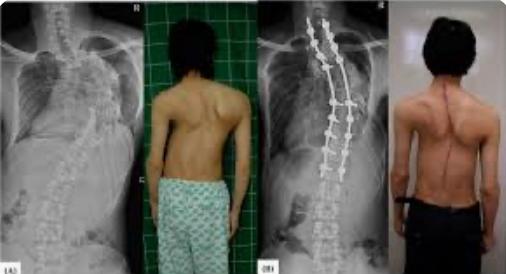

يعرف الجنف الخلقي بأنه تشوه خلقي في العمود الفقري يحدث بسبب إضطراب النمو الطبيعي للفقرات خلال الأسبوع الرابع إلى السادس من الحمل.

ويتم التشخيص باستخدام الصور الشعاعية الكاملة للعمود الفقري،التصوير الطبقي المحوري،والتصوير بالرنين المغناطيسي مطلوب لتقييم تشوهات المحور العصبي (الحبل الشوكي).

-يمكن أن يكون العلاج بالملاحظة والمتابعة أو بالتدخل الجراحي اعتمادًا على النمط التشريحي المحدد وتطور المنحنى.

لعلاج الجراحي:

عن طريق الاندماج Fusion الخلفي أو الأمامي للفقرات (+/- قطع العظام والتصحيح المتواضع).

-أوعن طريق نظام الشد والسحب والتقويم للعمود الفقري بواسطة قضبان معدنية .

Distraction based growing rod construct